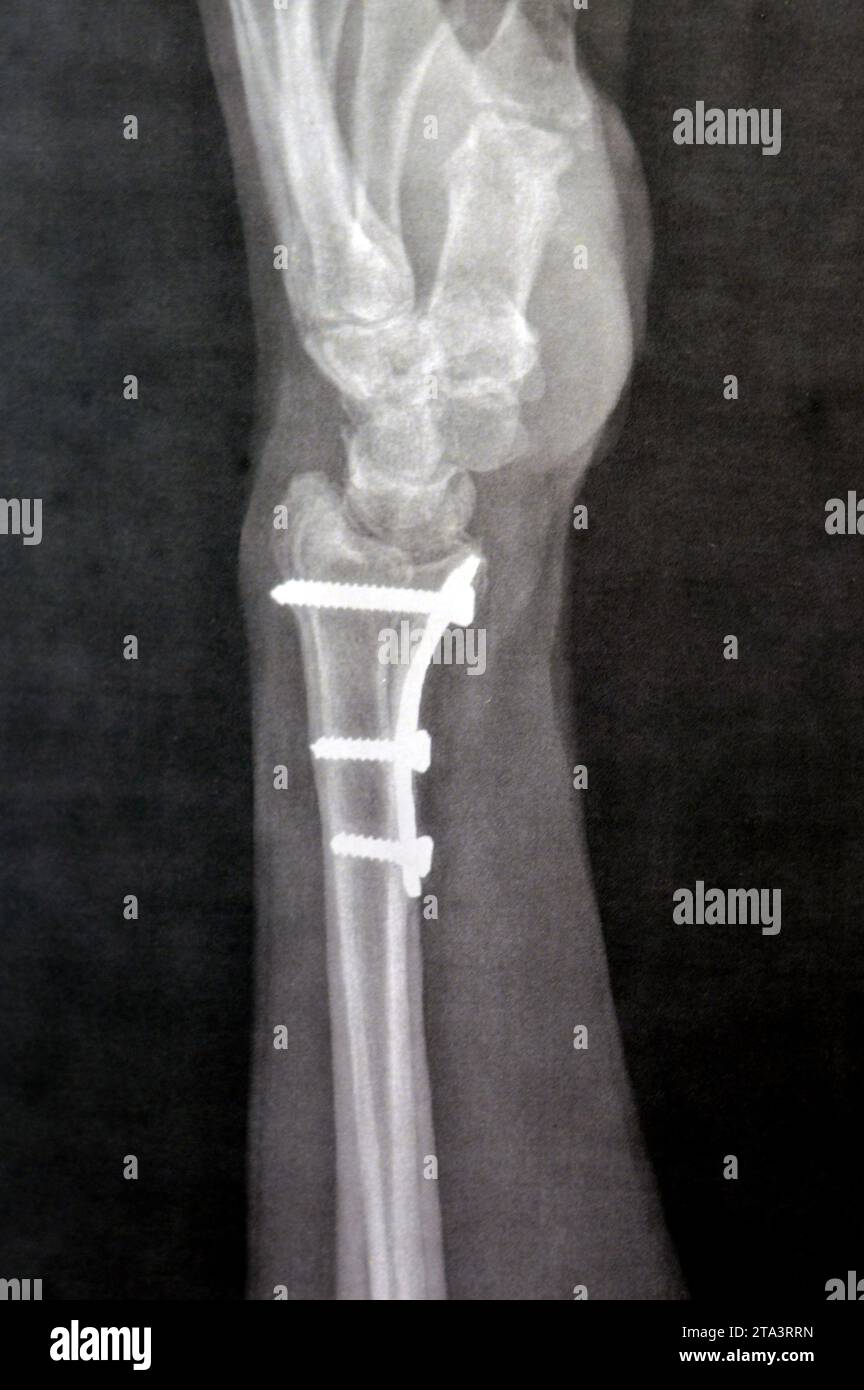

Fissure Fracture X Ray . 'toddler's fracture' = tibial spiral fracture in a toddler. It is necessary when studying the x. Stress fractures of the tibia result from repeated low force trauma. When a person has a bone fracture, one of the first things a person will want to know is how bad it is. Proper description of fractures with knowledge of injury mechanisms, consequent care and complications. It provides an exit route for the chorda tympani from the middle ear to. Transverse, oblique and spiral fractures. The petrotympanic fissure (glaserian fissure) can be visualized on axial and sagittal images (figs. A fissure fracture is noted at the middle third of the right metatarsal bone, more clear on the oblique view (yellow arrow). To determine the severity and treatment/recovery time, doctors will typically perform an. Tibial fractures usually result from high force trauma. Importance of standard radiography of the wrist.

Trauma and Fractures Orthopaedic Center of the Virginias Fissure Fracture X Ray It is necessary when studying the x. Importance of standard radiography of the wrist. To determine the severity and treatment/recovery time, doctors will typically perform an. Tibial fractures usually result from high force trauma. 'toddler's fracture' = tibial spiral fracture in a toddler. A fissure fracture is noted at the middle third of the right metatarsal bone, more clear on. Fissure Fracture X Ray.

Xray of a wrist with a distal radius fracture that has healed in Fissure Fracture X Ray Proper description of fractures with knowledge of injury mechanisms, consequent care and complications. The petrotympanic fissure (glaserian fissure) can be visualized on axial and sagittal images (figs. A fissure fracture is noted at the middle third of the right metatarsal bone, more clear on the oblique view (yellow arrow). It is necessary when studying the x. 'toddler's fracture' = tibial. Fissure Fracture X Ray.